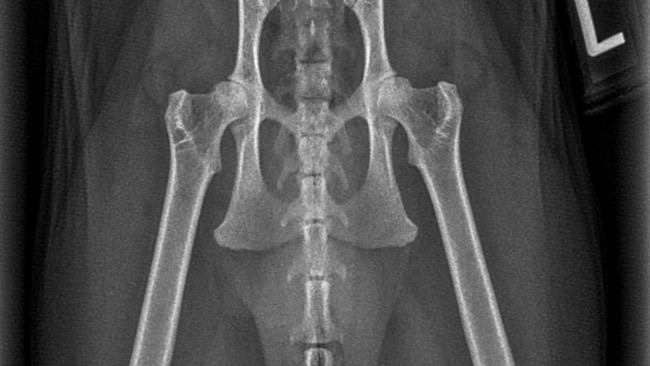

Na pewno wiele osób zna historię mojej kotki Sabinki. Po brutalnym opróżnieniu gruczołów okołoodbytowych przez lekarza, który nie miał o tym pojęcia i nie zabiezpieczyl jej w żaden sposób po zabiegu kotka przez blisko trzy tygodnie gubiła kał po domu. I tak naprawdę od tego momentu zaczęło się gryzienie ogona…

We wrześniu ubiegłego roku ten problem nasilił się do takiego stopnia, że praktycznie nie może zostać sama w domu ponieważ może sobie ten ogon odgryźć. Jestem załamana bo nie wiem jak jej pomóc.

Odwiedziłyśmy masę lekarzy, konsultowaliśmy się z behawiorystami, dietetykami, oraz lekarzami którzy zajmują się leczeniem zaburzeń psychicznych u Kotów. Ostatnia wizyta u neurologa zakończyła się skierowaniem na badanie, na które mnie już po prostu nie stać. Od blisko sześciu miesięcy wydaję pieniądze na przeróżnych specjalistów i nikt nie potrafi nam pomóc. W tym badaniu możliwe, że potwierdzimy czy Sabinka wymaga operacji amputacji ogona. Sabinka od kilku dni jest również na lekach psychotropowych, jak na razie bez żadnej poprawy. Chciałabym, żeby moja koteczka mogła wieść spokojne i dobre życie. A że jest dla mnie jak dziecko, (bo mam tylko ją) naprawdę próbuję wszystkiego. Jestem osobą samotną, która również wymaga stałych konsultacji lekarskich ze względu na dwa guzy w głowie. Podejrzewają nowotwór centralnego układu nerwowego. Bardzo proszę wszystkich którym los Sabinki nie jest obojętny o wsparcie. Liczę że w Internecie jest taka siła i w końcu uda nam się przynajmniej ją wyprowadzić na prostą.